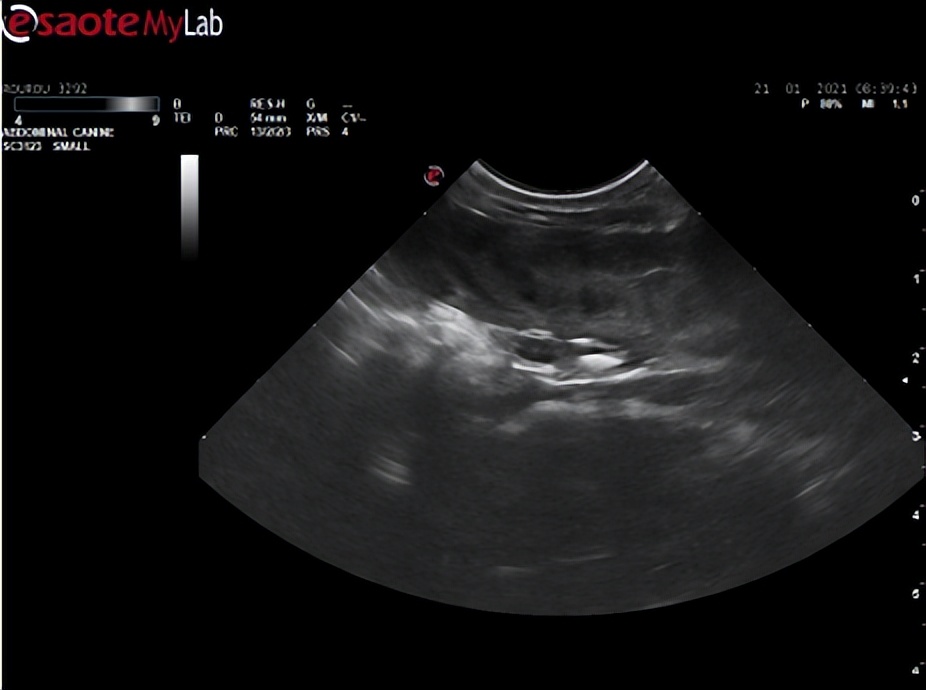

【超声检查】

超声检查,子宫内回声不均匀,有少量液性暗区不规则分布。